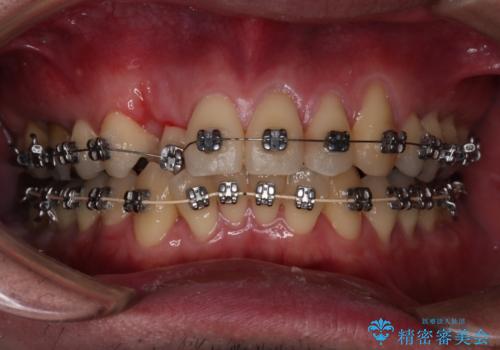

【メタル装置】1本のみ抜歯してワイヤー矯正

- 30代男性

- 矯正装置

- メタル装置

- 右上2番目の歯が舌側転位していることと前歯の叢生(がたつき)を主訴に来院されました。

右上の犬歯が初診時よりかなり歯根露出しており、矯正の力をかけるとさらに歯根露出するリスクがあるため、右上の2番目の歯を前に出すためにも

右上の犬歯を抜歯して歯並びを整える治療計画を立てました。

下のがたつきをとるために、IPR(歯と歯の間を削る処置)も行って歯を並べていきます。

抜歯の本数を最小限に抑えたことで、治療計画も1年5ヶ月と短期間で終了することができ

主訴である前歯のがたつきも改善され綺麗な歯並びになりました。

矯正の装置を除去したタイミングで、ホワイトニングも行うことで歯の色味も白くなりました。